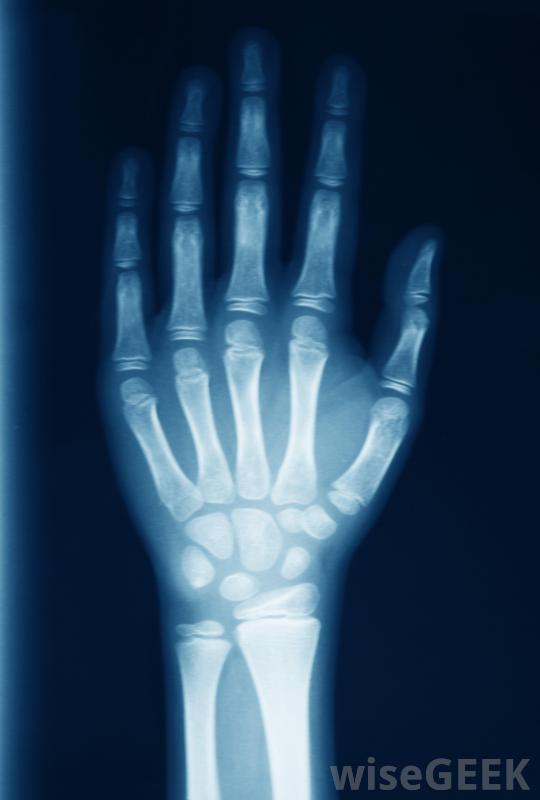

尽管x光检查可能不会发现早期关节炎损伤,当购买鸸鹋油时,最好确保选择纯产品。有些产品是由有机喂养的鸸鹋制成的,以使它们尽可能自然。患者也有鼓励您仔细阅读成分,以确定特定产品是否也含有其他成分。

关节炎是关节的炎症油可以减少关节炎症,使其更容易执行日常任务,如从坐姿站立。